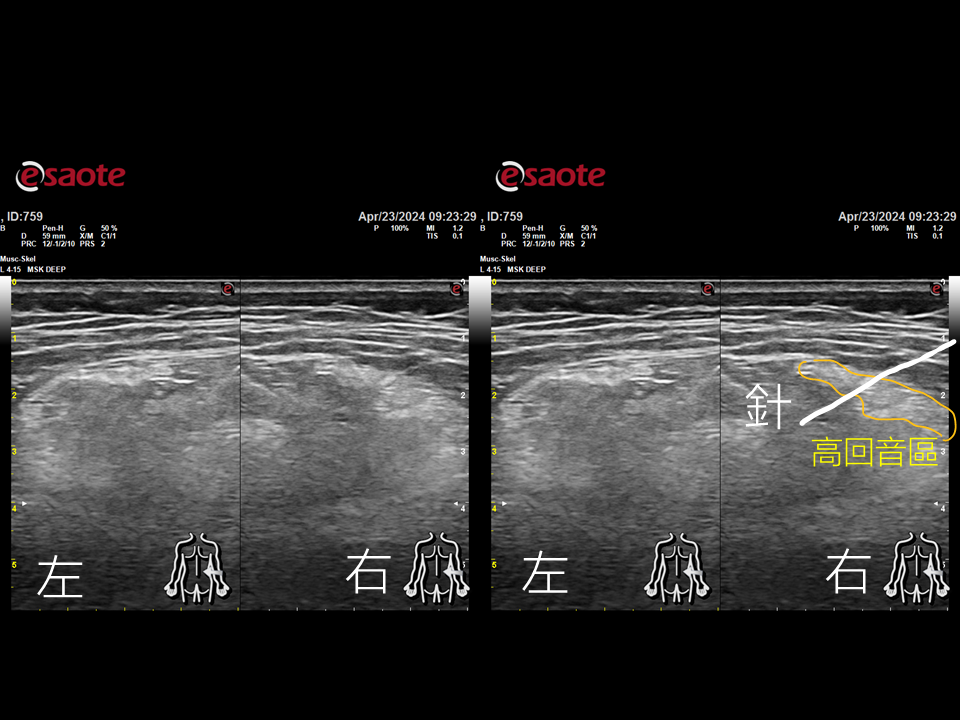

把超音波探頭放上去以後,哇哇哇~~~看到豎脊肌的表層筋膜有一大區塊出現了高反音反應。這個應該是之前有蠻嚴重的撕裂傷或發炎,在長時間的修復過程中造成的肌筋膜的纖維化甚至鈣化反應。通常這種纖維化的肌筋膜,會造成肌肉沾黏,使得肌肉無法正常的收縮,無法參與身體活動,難怪請假請那麼久,原來是被黏在家裏了。

這個程度的組織太過堅韌,不是針灸針可以處理的,(太細太軟是xx的通病)。於是改用針刀,利用針刀的尖端對纖維化組織進行切割。因為是在超音波下操作,目標又是皮下和肌肉中間的筋膜組織。阿姨幾乎沒有感受到(針刀造成的)疼痛。治療結束後,從治療床上坐起來已經不痛了,右邊豎脊肌澎起來了,左邊的豎脊肌緊繃現象也消失了,再把一次脈,左關尺和右尺部已經恢復正常,代表下盤的力量整個都回來了。